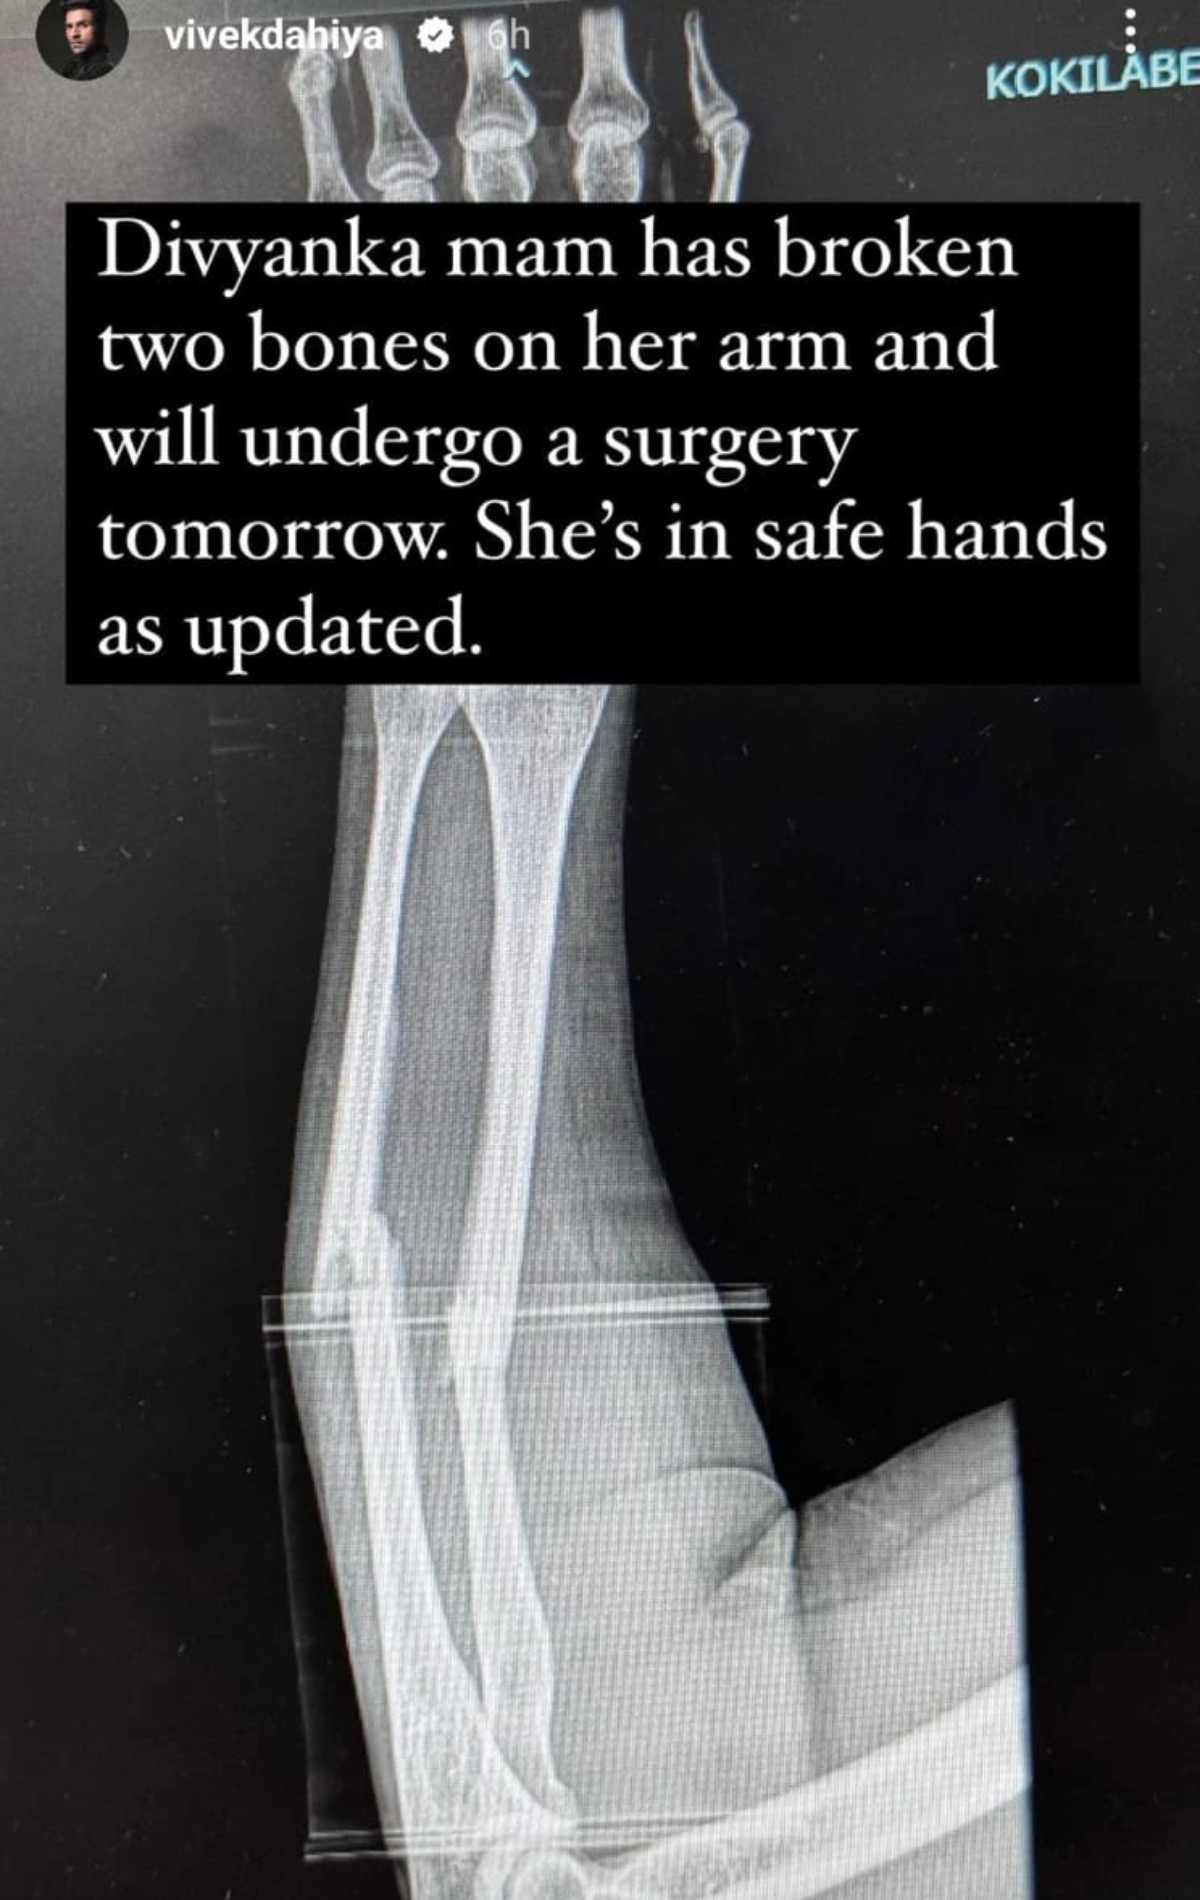

Television actor Divyanka Tripathi Dahiya met with an accident, as disclosed by her publicist on Instagram to her and her husband Vivek Dahiya’s followers. While the PR team has refrained from sharing many specifics, they have mentioned that Divyanka is currently receiving medical attention. Soon, Vivek posted a picture of Divyanka's X-ray, revealing that she suffered a fractured arm in the accident and is scheduled for surgery today, April 19. Following the incident, Vivek cancelled his planned live session on Instagram for today to support her during this time.

On April 18, Vivek posted an Instagram story stating, "Divyanka mam has fractured two bones in her arm and will undergo surgery tomorrow. She's in good hands, as updated."